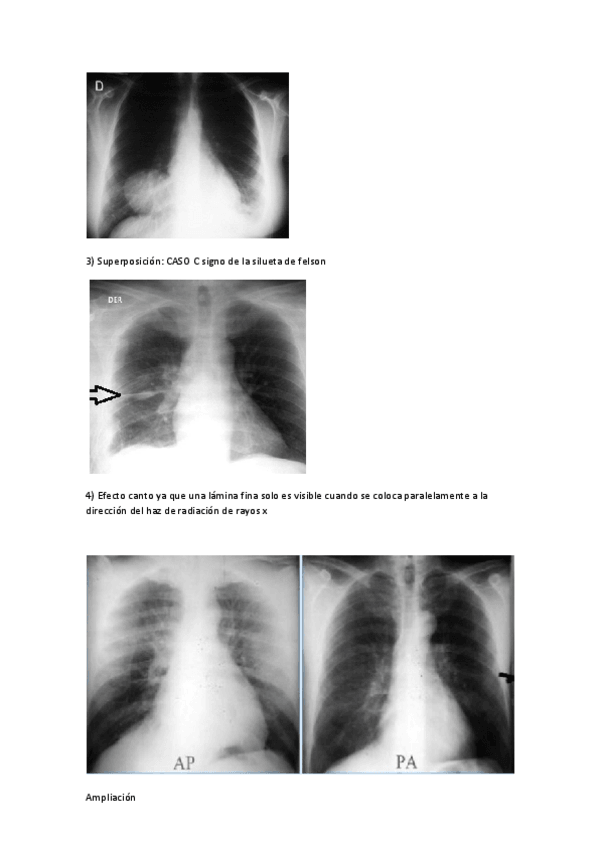

He publicado nuevos apuntes de Fundamentos Físicos y Equipos: Informacion-adicional-GEOMETRIA-DE-LA-IMAGEN.pdf

He publicado nuevos apuntes de Fundamentos Físicos y Equipos: EJERCICIO-GEOMETRIA.pdf